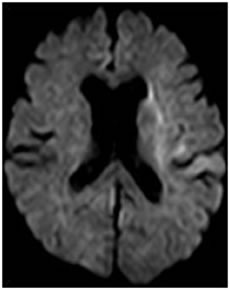

脳梗塞は発症してもすぐにCTやMRIで所見が出るわけではありません。最も感度の良い「拡散強調画像」という特殊な検査法でも、発症から約30分から1時間ほど経たないと異常は発見できません。従って、ごく早期の脳梗塞は「脳卒中の症状があり、CTで出血がなければ脳梗塞」と診断するわけです。また、CTでは診断に限界がある場合も多く、MRI検査が必要です。当院では症状のある患者さんは最優先にMRI検査(24時間稼働)をしております。(図1)

図1:脳梗塞のMRI拡散強調画像。矢印の部位が淡く白くなっています。 |